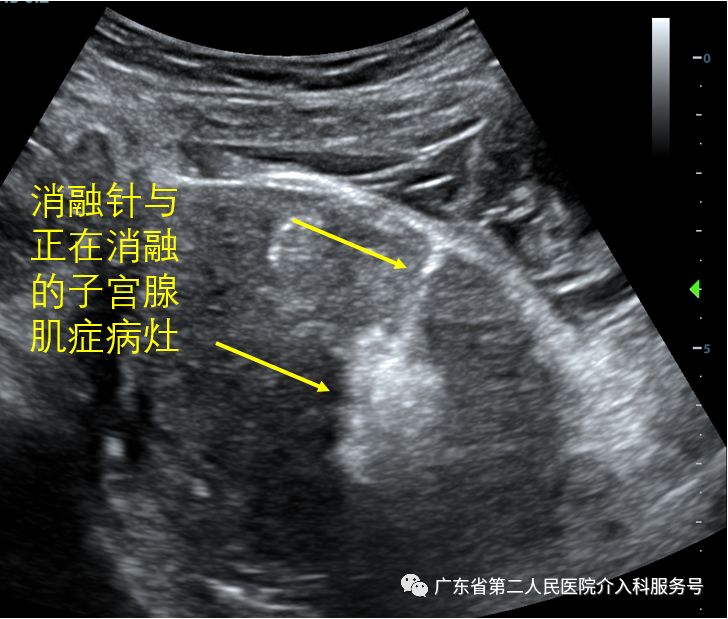

下图为消融时的消融针与正在消融的子宫腺肌症病灶。